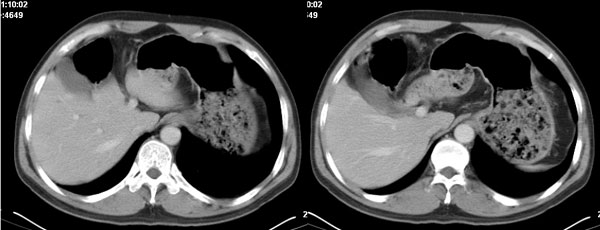

李**,男,46岁,便血1天入院,慢性贫血貌,腹平、软,剑突下压痛,肠鸣音稍活跃,hb大于1g/l,胃镜:慢性浅表性胃炎,b超:1肝内多发性占位 2腹腔内囊性肿块 ,肝内圆形影平扫ct值42.9,动脉期48.6,静脉期58.2,延迟期62.2

影像学表现:1 腹腔前中部、胰腺前方囊实性病灶(个人认为确定有否实性成分存在这是关键,涉及到鉴别诊断,如果是口服阳性造影剂则可明确左侧是不是小肠了),囊性部分囊壁不均,实性部分有强化,与小肠关系较密切,局部小肠受推移;与胰头、胃后壁均有脂肪间隙存在;2 胰腺无异常改变,胰周无渗出;3肝后段包膜下2个小圆形低密度灶,从图像和楼主提供的ct值来看有轻度强化,灶周无片状强化,不似单纯囊肿及肝癌、炎性病变表现;4 腹膜后及腹腔内无淋巴结肿大。

胰腺边界清晰,胰周筋膜不厚,胰周脂肪密度无明显增高;其前方囊实性病灶,边界清晰,增强后实性部分轻度强化;肝内多发边界清晰低密度影,增强后无明显强化(平扫ct值42.9,动脉期48.6,静脉期58.2,延迟期62.2)。

原因:胰头前方,前上腹部巨大囊实性肿物,与小肠关系密切,与胰头及胃壁之间脂肪间隙存在,囊壁不均匀,部分强化,占位效应明显,小肠上段扩张,十二指肠及胃腔内大量食物存留,说明上消化道有部分梗阻。因此,考虑来源于肠道的肿瘤。再结合其病史及肝内改变,这样考虑更有道理。